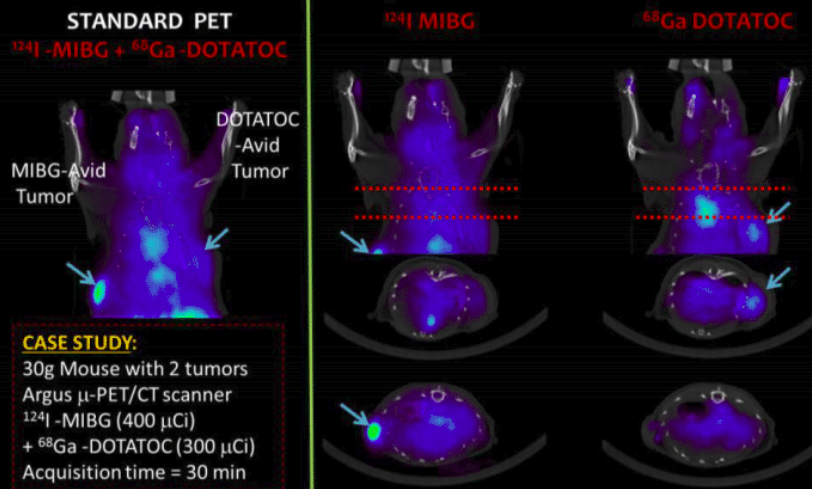

| ABSTRACT | Introduction: Simultaneous in-vivo imaging of several biological processes may improve oncological, neurological and cardiovascular studies by providing complementary information obtained under the same exact conditions and coregistered in space and time. Standard PET imaging does not allow multiplexed acquisitions, as all annihilation photons have the same energy. We developed a technique called multiplexed PET (mPET), which uses a tracer labelled with a pure positron emitter (such as 18 F, 13 N, 11 C), and a tracer labeled with a positrongamma emitter (such as 124 I, 76 Br, 82 Rb, 86 Y). Positrongamma emitters generate a significant number of triplecoincidences , which allows them to be differentiated from the standard PET radionuclides . In this work, we evaluated the performance of mPET using phantom and animal experiments. |

| JOURNAL | IEEE Nuclear Science Symposium & Medical Imaging Conference, 2014 |

| ABSTRACT | Positron emission tomography (PET) is one of the most sensitive noninvasive molecular imaging tool, being its sensitivity several orders of magnitude higher than that typically obtained in single photon emission computed tomography (SPECT). However, PET lacks the ability of SPECT to multiplex signals from several tracers, which is very useful in many different studies such as cardiac imaging with 99mTcSestamibi and 201Tl. Recently, it has been shown that the use of tracers labelled with positrongamma emitter radionuclides like (124I, 86Y, 82Rb, 94mTc, 76Br) in combination with tracers labelled with standard positronemitter radionuclides like (18F, 11C, 13N) enables multiplexed PET (mPET). mPET uses the triple coincidences from the positrongamma emitters, together with the standard double coincidences to reconstruct separated images of each radionuclide’s activity distribution. We obtained encouraging results with mPET in some initial preclinical studies, but a detailed study of the quality and quantification properties of mPET images, and an evaluation of its performance in realistic clinical scenarios was still required. |